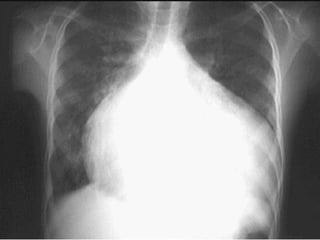

CASO C : Mujer de 78 años, con  HAS de 20 años  de evolución.  Disnea de pequeños   esfuerzos y  palpitaciones.  PA 160/90, FC 118 X min. Soplo sistólico apical.  Fibrilación auricular.   Hepatomegalia. TRATAMIENTO:  Digoxina, I. ECA, diurético de asa, espironolactona, nitratos, aspirina o warfarina sódica.

CASO C :Mujer de 78 años, con HAS de 20 años de evolución. Disnea de pequeños esfuerzos y palpitaciones. PA 160/90, FC 118 X min. Soplo sistólico apical. Fibrilación auricular. Hepatomegalia. TRATAMIENTO: Digoxina, I. ECA, diurético de asa, espironolactona, nitratos, aspirina o warfarina sódica.